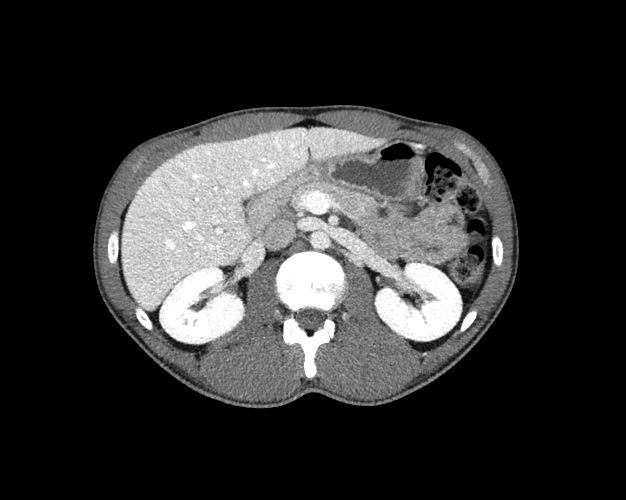

Body

Covers abdominal CT anatomy.